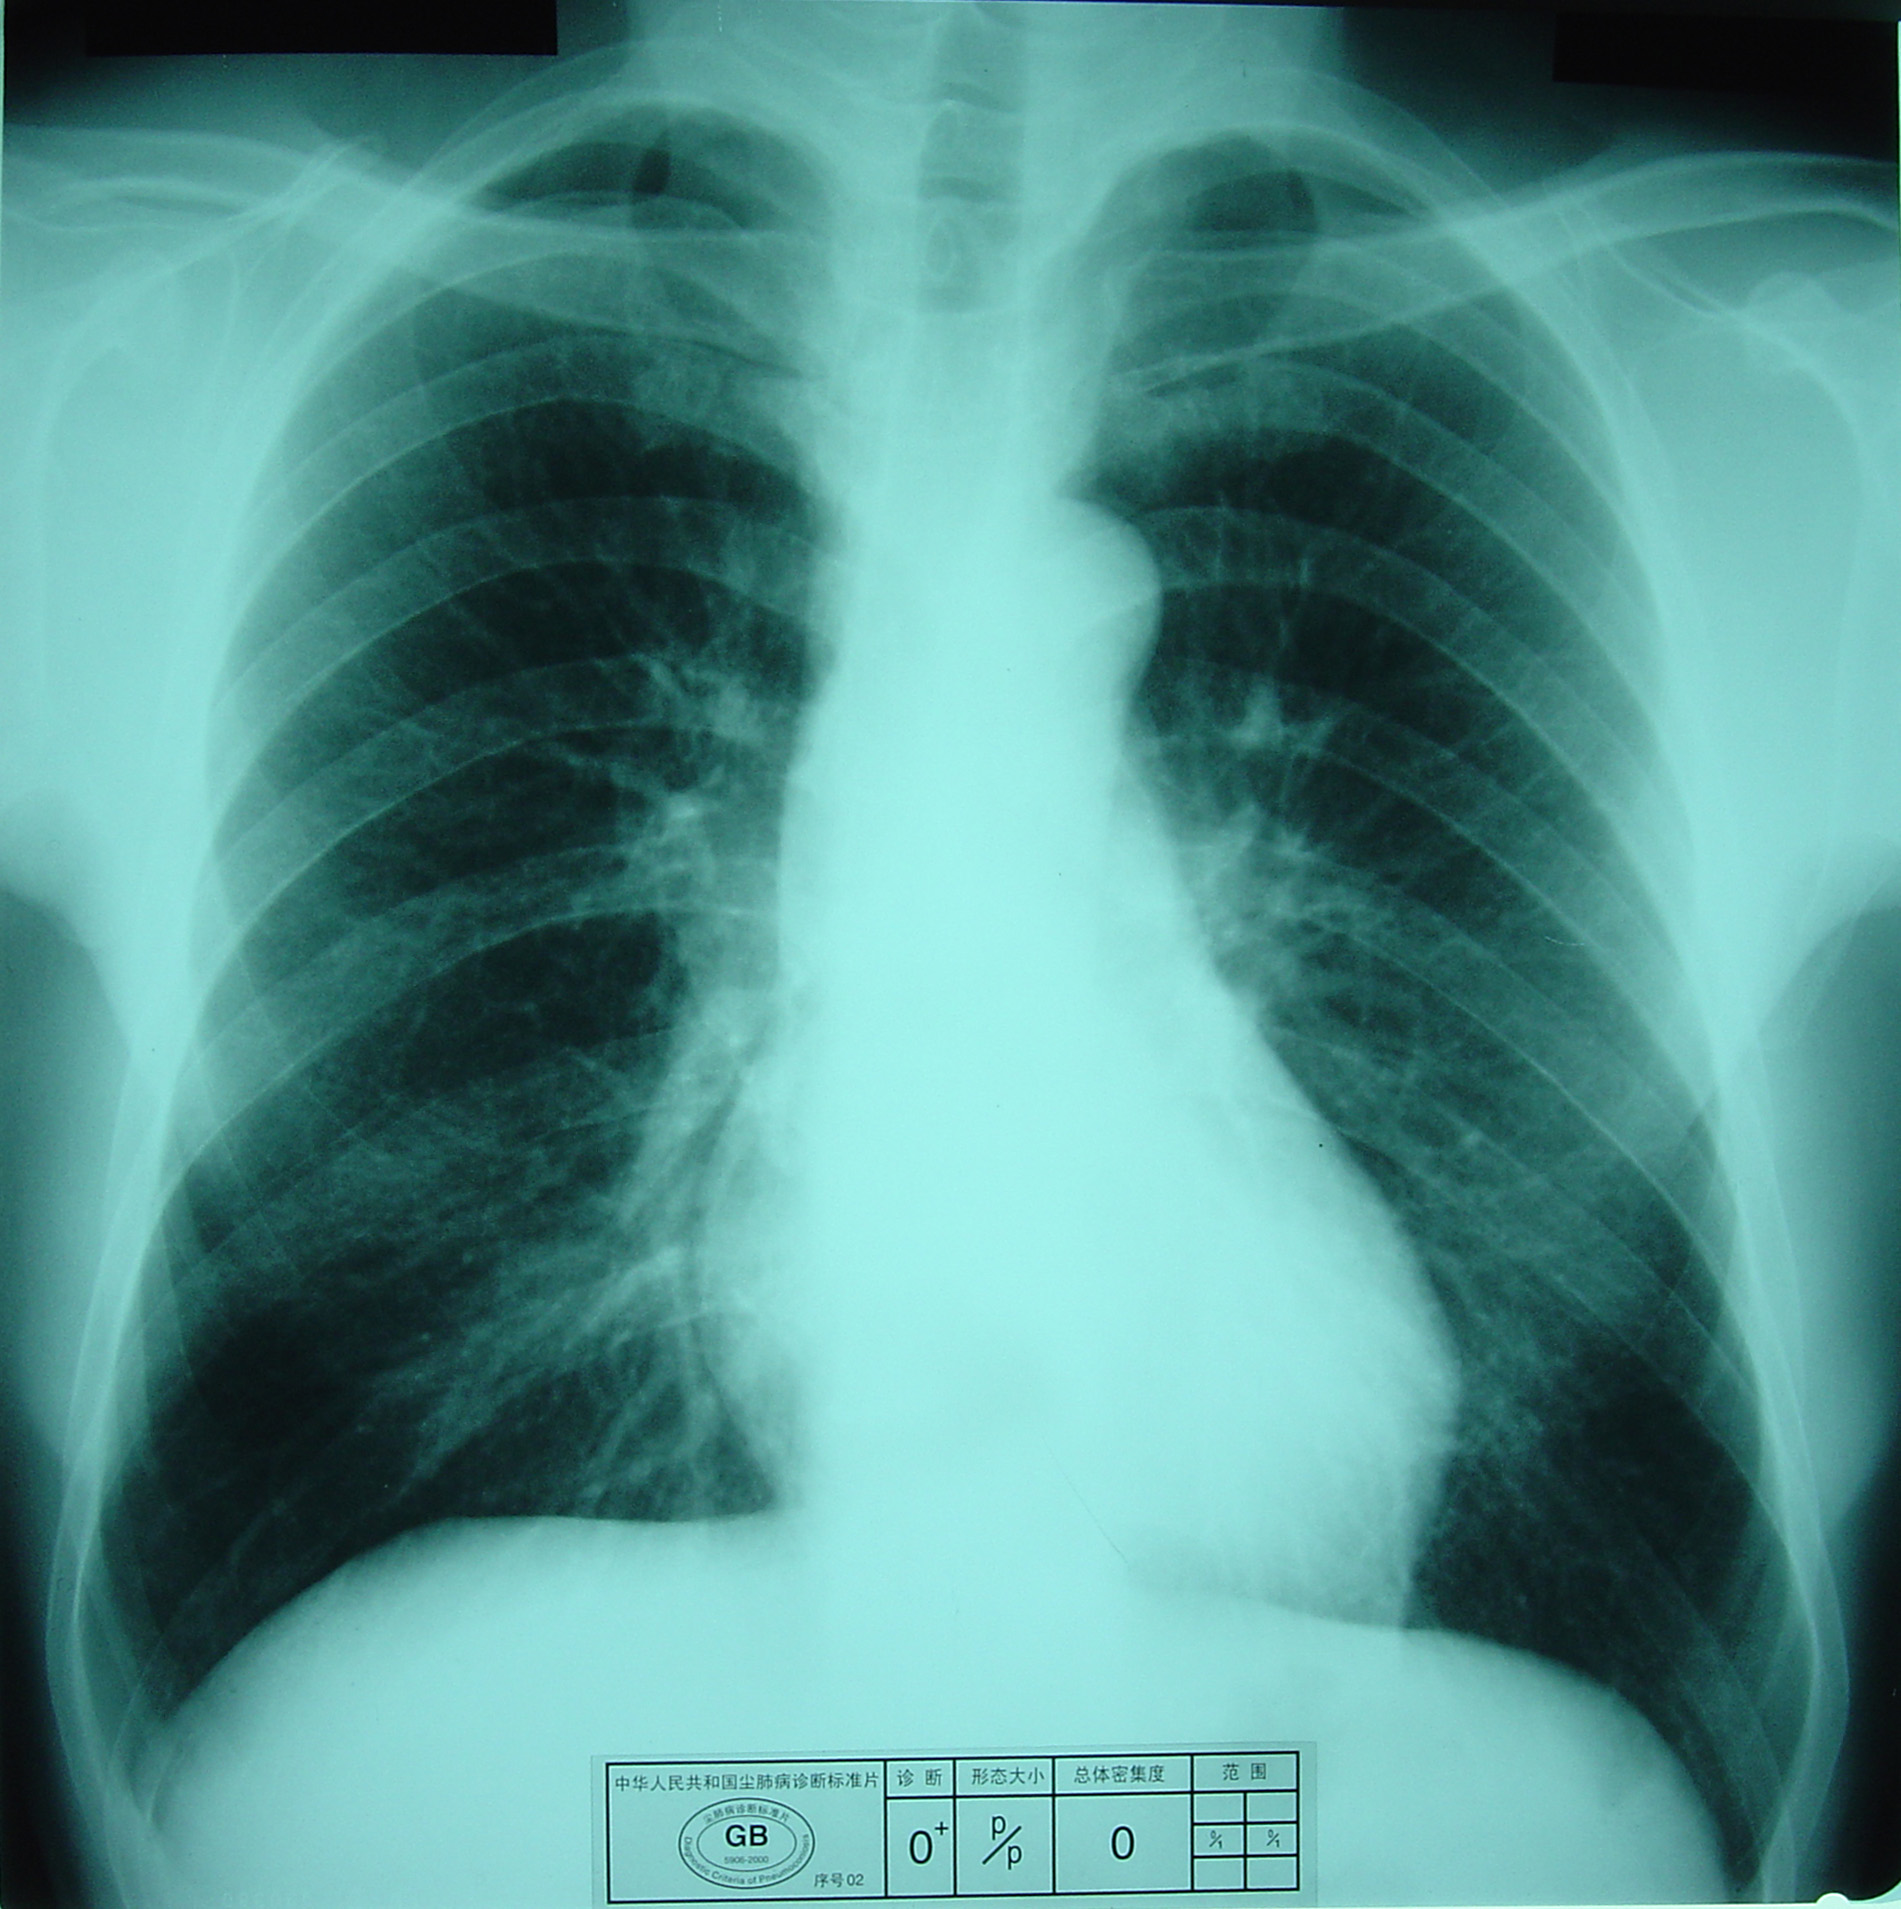

(2)X射线胸片表现:矽肺X射线胸片影像是肺组织矽肺病理形态在X射线胸片的反映,是“形”和“影”的关系,与肺内粉尘蓄积、肺组织纤维化的病变程度有一定相关关系,但由于多种原因的影响,并非完全一致。这种X射线胸片改变表现为X射线通过病变组织和正常组织对X射线吸收率的变化,呈现发“白”的圆形或不规则形小阴影,作为矽肺诊断依据。X射线胸片上其他影像,如肺门变化、肺气肿、肺纹理和胸膜变化,对矽肺诊断也有参考价值。在X射线胸片上,肺野内直径或宽度不超过10mm的阴影。小阴影按其形成分为圆形和不规则形两类。

1)圆形小阴影:是矽肺最常见和最重要的一种X线表现形态,其病理基础以结节型矽肺为主,呈圆或近似圆形,边缘整齐或不整齐,直径小于10mm,按直径大小分为p(<1.5mm)、q(1.5~3.0mm)、r(3.0~10mm)三种类型。p类小阴影主要是不太成熟的矽结节或非结节性纤维化灶的影像,q、r类小阴影主要是成熟和较成熟的矽结节,或为若干个小矽结节的影像重叠。圆形小阴影早期多分布在两肺中下区,随病变进展,数量增多,直径增大,密集度增加,波及两上肺区。